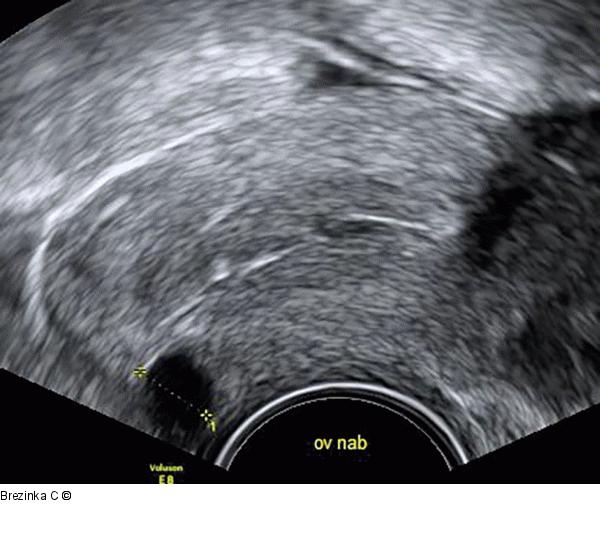

Abbildung 2: Ovulum Nabothii Ein 8 mm großes Ovulum Nabothii an der vorderen Muttermundslippe. |

Ein 8 mm großes Ovulum Nabothii an der vorderen Muttermundslippe. |